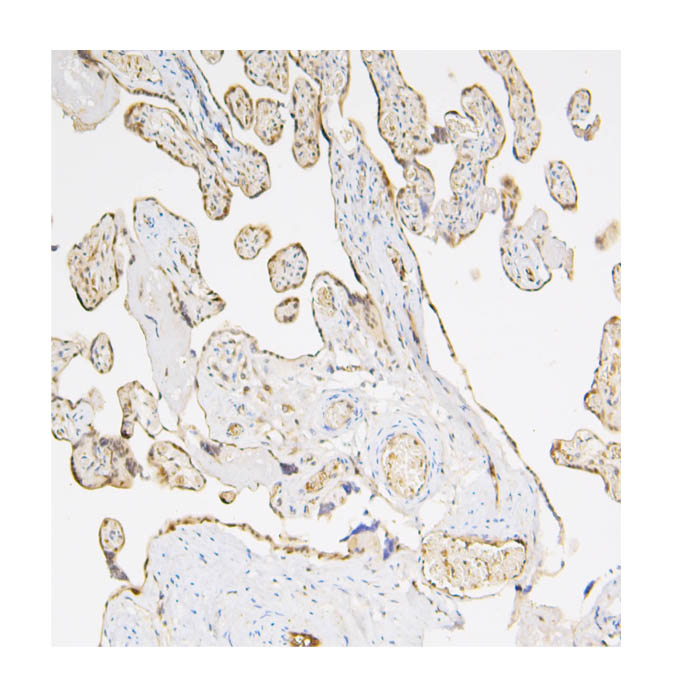

IHC analysis of Caspase 3/CASP3 (p17) using anti-Caspase 3/CASP3 (p17) antibody (M00334-6).

Caspase 3/CASP3 (p17) was detected in a paraffin-embedded section of human placenta tissue. Biotinylated goat anti-mouse IgG was used as secondary antibody. The tissue section was incubated with mouse anti-Caspase 3/CASP3 (p17) Antibody (M00334-6) at a dilution of 1:200 and developed using Strepavidin-Biotin-Complex (SABC) (Catalog # SA1021) with DAB (Catalog # AR1027) as the chromogen.